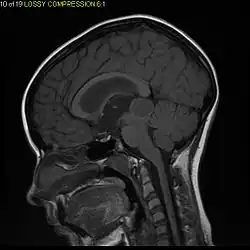

Usually – depending on the interview of the patient and after a clinical exam which includes a neurological exam and an ophthalmological exam – a CT scan and/or an MRI scan will be performed to confirm the presence of a tumor. They are usually easily distinguishable from normal brain structures using these imaging techniques. A special dye may be injected into a vein before these scans to provide contrast and make tumors easier to identify. Pilocytic astrocytomas are typically clearly visible on such scans, but it is often difficult to say based on imaging alone what type of tumor is present.